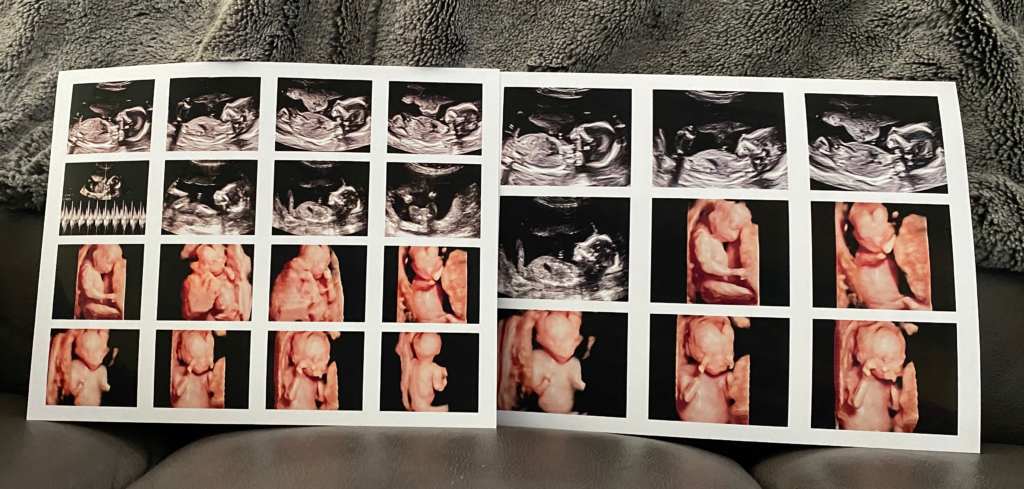

A Note From Kelly

Hello and thank you for considering me for your elective ultrasound. I am a Registered Diagnostic Sonographer (RDMS). I graduated from ultrasound school in 2005. A common question I am often asked, is how I got starteddoing in-home ultrasounds. Being a mom is what brought me into your home. When my son was three years old, I needed something that was more flexible for myself and my family. I thought an in-home option would be best. Having worked Outpatient doing anatomy scans and other ultrasounds, I knew I didn’t want moms to feel rushed. I wanted families to feel comfortable in their own space. Seeing your unborn baby, should be a family affair. Fast forward ten years later and I have built and amazing business, thanks to all my wonder clients. My son is now fourteen and my husband is proud of my small business. We also have a Miniature Schnauzer, Coco. Last Summer we bought a RV and have enjoyed camping.